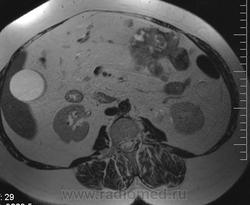

очень характерная картина для метастаза рака яичника, к сожалению.

Не могу достоверно определить локализацию метастаза брюшной полости, вероятно в лимф. узел с инвазией оободочной кишки. Рецидив С-r левого яичника думаю, что с инфильтацией левой стенки прямой кишки и культи влагалища, вторичная лимфаденопатия л/у малого таза. каликопиелоуретероэктазия (инвазия нижних отделов левого мочеточника?) Холедох широковат, но желтухи по внешнему виду нет.

Прорастание левого мочеточника рецидивной опухолью есть 100%, метастаз в большой сальник характерен для рака яичников, как и сигнальные характеристики его. Культя в данном случае шейки матки.

Большое спасибо. По поводу стриктуры холедоха мучают сомнения.